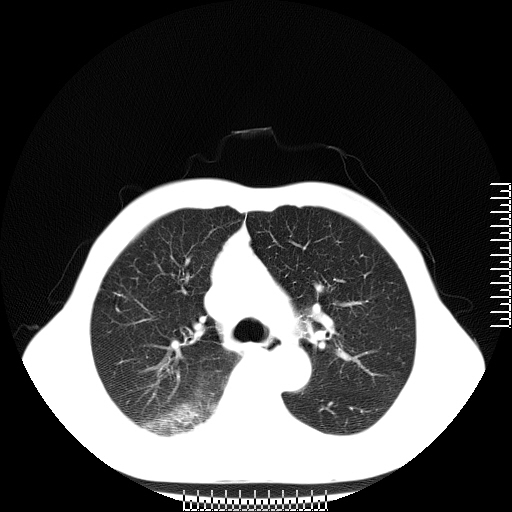

CT50771:肺部病变,手术病理结果已公布

本帖最后由 cefcmj 于 2015-7-10 08:27 编辑 (病理结果: http://www.radida.com/bbs/forum. ... d=126553&extra=) 性别:男 年龄:67岁 主 诉:咳嗽、咯血4天 现病史:4天前无诱因出现咳嗽,咯血,一日10口 ...

[病理诊断] CT50771:右肺中分化鳞状细胞癌。

考虑右肺下叶背段周围型肺癌并癌性空洞形成,右肺下叶肺泡积血。支持。

考虑右肺下叶背段周围型肺癌并癌性空洞形成,右肺下叶肺泡积血。

考虑继发性肺结核伴空洞形成、肺出血。

结核伴空洞形成?